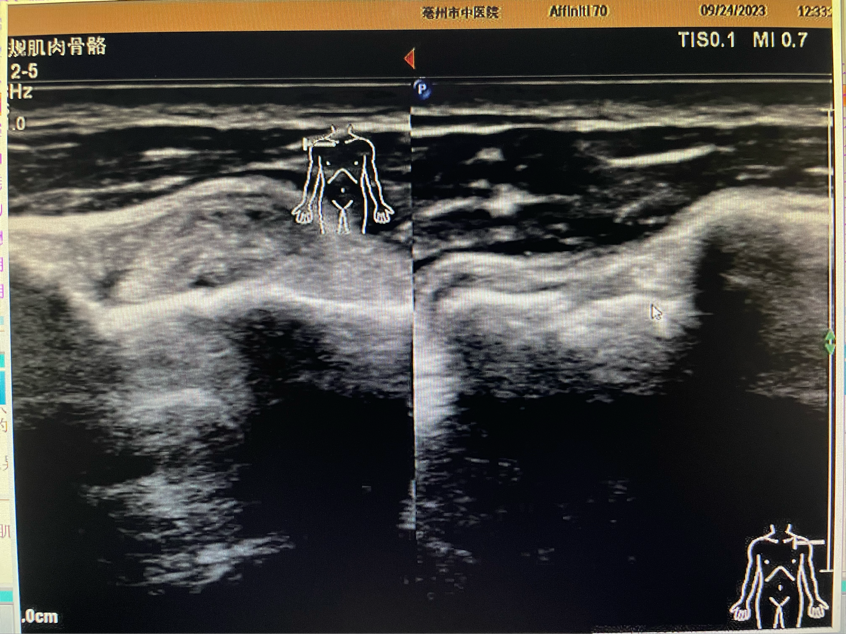

雙側肱骨頭結節(jié)間溝處肱二頭肌長頭肌腱短軸雙幅對比圖

肌骨超聲檢查是我院超聲科新開展的檢查項目。超聲科劉剛醫(yī)生為患者進行詳細肌骨超聲檢查,檢查所見:左側肱骨頭大小結節(jié)間溝空虛,代之以液性暗區(qū),較厚處約1.5mm,肱二頭肌長頭肌腱連續(xù)性中斷,斷端遠端攣縮,周圍可見厚約3.6mm液性暗區(qū)。檢查意見:左側肱二頭肌長頭肌腱完全斷裂伴周圍積液。